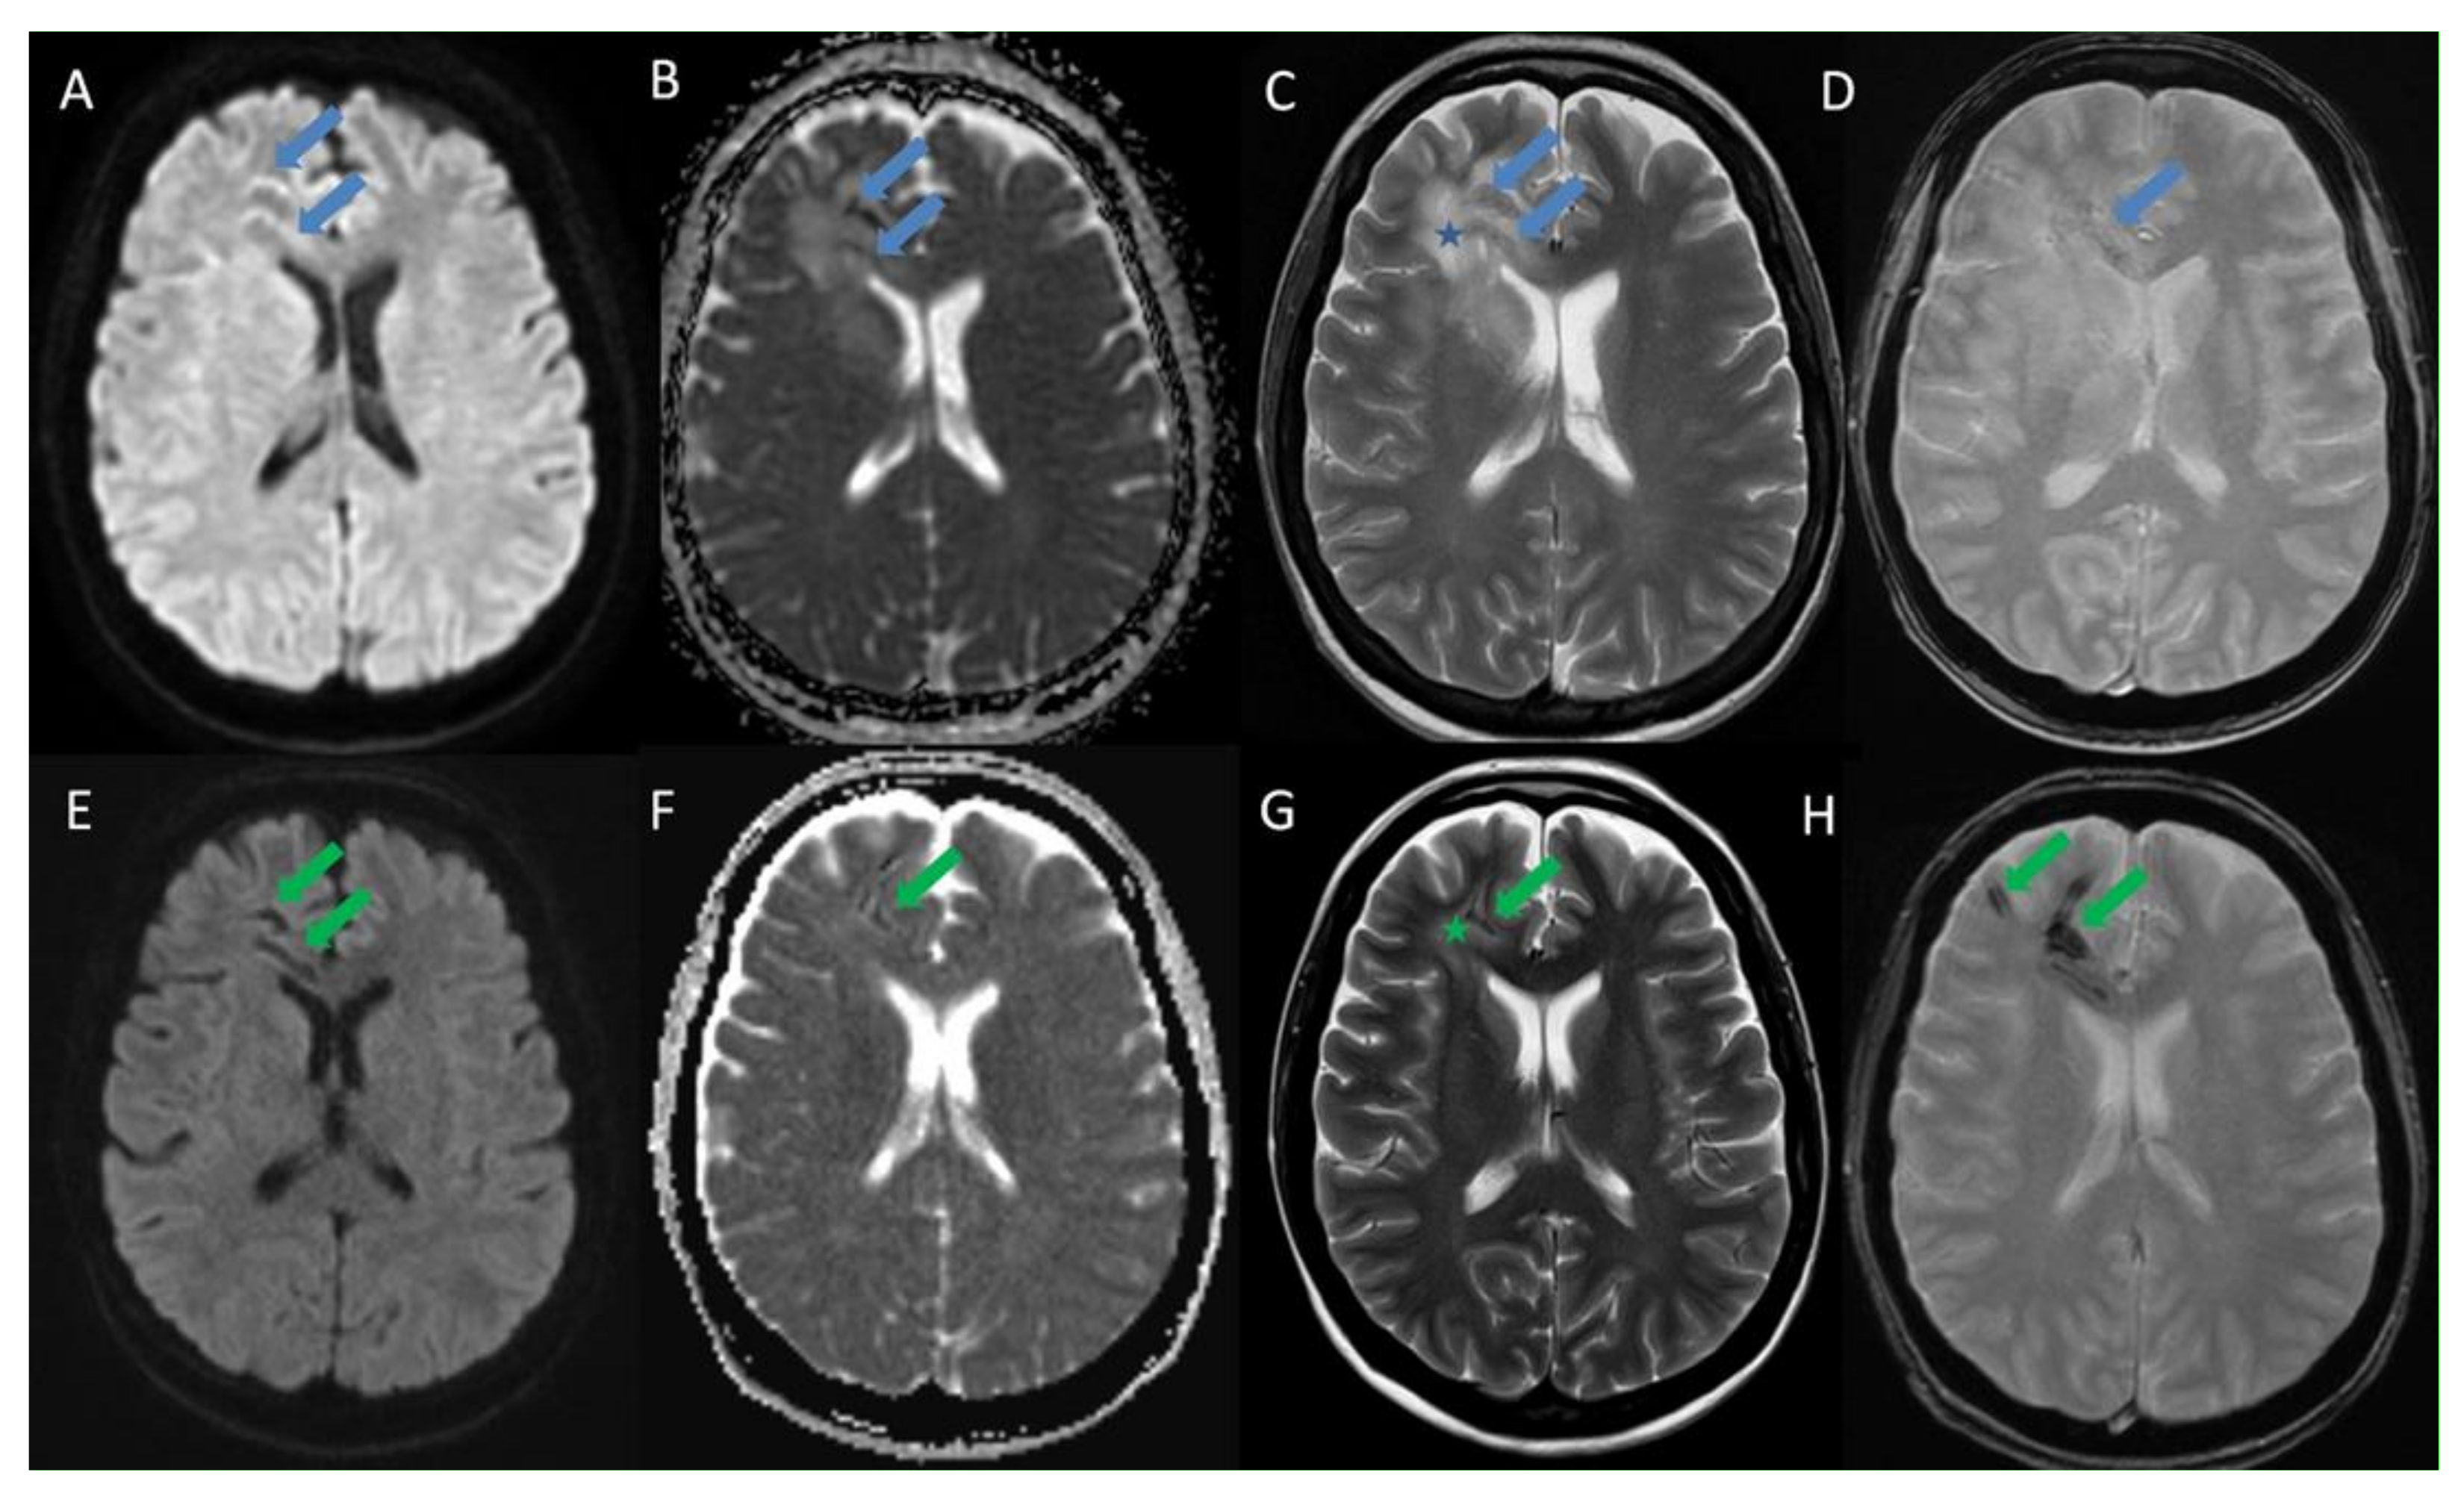

Listeria Monocytogenes Brain Abscesses in a Patient with Disseminated Non-Small Cellular Lung Cancer: MRI Findings

- Slezák, O.; Žižka, J.; Kvasnička, T.; Dvořáková, R.; Česák, T.; Ryšková, L.; Ryška, P.; Eliáš, P. Worm-like appearance of Listeria monocytogenes brain abscess: Pesentation of three cases. Neuroradiol. 2020, 62, 1189–1193. [Google Scholar] [CrossRef] [PubMed]